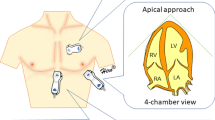

The ultrasound scanning protocol, in sequence, included four views with seven images: parasternal long axis 2D with and without color-flow Doppler over the mitral and aortic valve simultaneously, apical 4 chamber 2D with and without color-flow Doppler over the mitral valve, apical 4 chamber 2D with color-flow Doppler over the tricuspid valve, apical 5 chamber 2D with and without color-flow Doppler over the aortic valve, and subcostal view of the inferior vena cava with sniff. To facilitate reproducibility trainees were taught to obtain views in the pre-specified sequence during each patient exam. Views were selected to identify a predetermined set of six key pathologies, namely left ventricular (LV) dysfunction, pericardial effusion, aortic valve regurgitation, moderate to severe mitral valve regurgitation, moderate to severe tricuspid valve regurgitation, and mitral valve stenosis. A subjective assessment of LV function was based on visual estimation of an ejection fraction (EF): > 50% indicating normal LV function and < 50% indicating LV dysfunction. The LV functional assessment was determined using the parasternal long axis and apical 4 and 5 chamber views. The presence of pericardial effusion was documented regardless of size. Pericardial effusion was assessed using the parasternal long axis and apical 4 and 5 chamber views. Assessment of valvular dysfunction was done utilizing qualitative assessment. With regard to regurgitation, subjective vena contracta width and jet area occupying the respective atria (left atrium for mitral regurgitation and right atrium for tricuspid regurgitation) were utilized. Mitral valve regurgitation was assessed using the parasternal long axis view with color Doppler and the apical 4 chamber view with color Doppler over the mitral valve. Tricuspid regurgitation was assessed using the apical 4 chamber view with color Doppler over the tricuspid valve. Aortic regurgitation was assessed as being present or absent; grading of aortic regurgitation was not performed. The presence of aortic regurgitation was assessed using the parasternal long view with color Doppler and the apical 5 chamber view with color Doppler over the aortic valve. A subjective assessment for mitral stenosis was used, including the presence of subjective thickening and restricted motion of the mitral leaflets and color Doppler demonstrating flow acceleration across the mitral valve. Mitral stenosis was only assessed as present or absent, and grading of severity was not preformed. Assessment of mitral stenosis utilized the parasternal long axis view with and without color Doppler over the mitral valve and apical 4 chamber with and without color Doppler over the mitral valve. Didactic and practical sessions used both English and Kiswahili languages.

The percentages of images, by scanning view, that were determined by the cardiologists to be of sufficient quality (grade 3 or higher) for interpretation were as follows (Fig. 1a): parasternal long axis 2D 86.9%; parasternal long axis with color Doppler 82.0%; apical 4 chamber 2D 75.0%; apical 4 chamber with color Doppler 77.3%; apical 5 chamber 2D 69.9%; apical 5 chamber with color Doppler 69.4%; subcostal 2D 56.8%. The percentages of scans that were determined by the cardiologists to contain appropriate images of sufficient quality for interpretation as to whether key pathologies were present or absent were as follows: (Fig. 1b): pericardial effusion 89.9%; LV dysfunction 87.3%; aortic regurgitation 85.1%; mitral valve regurgitation 88.9%; tricuspid valve regurgitation 82.4%; presence of mitral valve stenosis 91.8%. By trainee, the overall percentages of images that were determined by cardiologists to be of grade 3 or higher quality ranged from 18.0% (29/161) to 94.2% (356/378), median 76.7%; 5 of 8 trainees achieved 75% or greater interpretable images (Fig. 2a). Score on the post-training 20Q Ultrasound Images assessment (p = 0.004) and number of ultrasound examinations performed prior to study training (p = 0.039) were each positively associated with image quality in univariate analyses (Table 2).